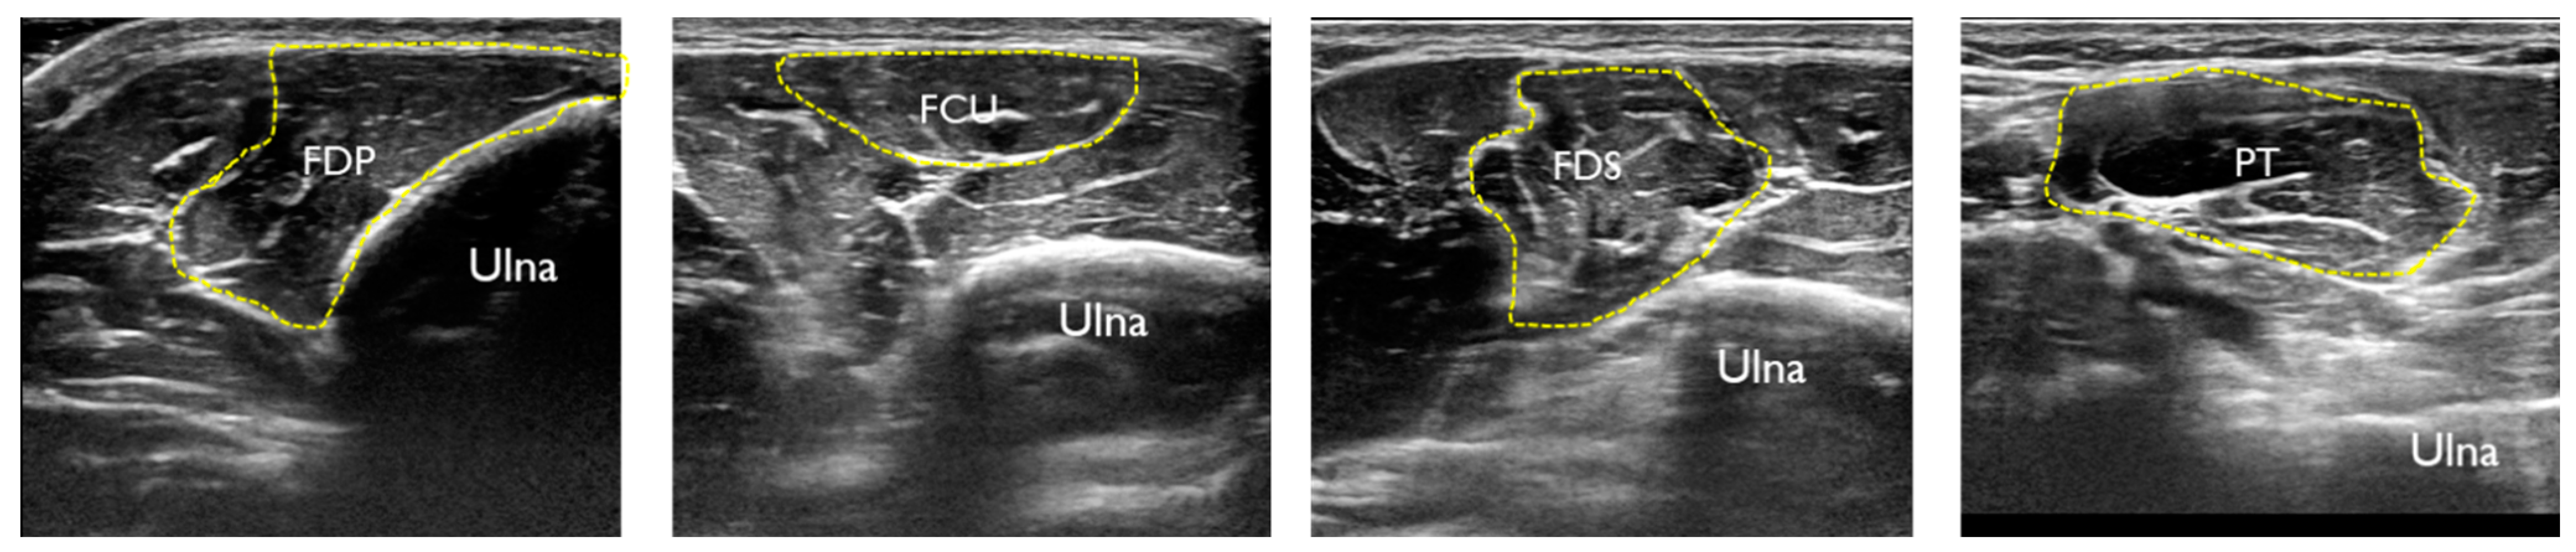

| Rest | Contraction | |||||

|---|---|---|---|---|---|---|

| ICC | 95%CI | SEM | ICC | 95%CI | SEM | |

| FDP | 0.93 | 0.69–0.98 | 0.17 | 0.89 | 0.56–0.98 | 0.20 |

| FCU | 0.99 | 0.94–0.99 | 0.05 | 0.98 | 0.92–0.99 | 0.07 |

| FDS | 0.94 | 0.76–0.99 | 0.19 | 0.94 | 0.77–0.99 | 0.13 |

| PT | 0.96 | 0.82–0.99 | 0.19 | 0.97 | 0.87–0.99 | 0.15 |

| UN | 0.90 | 0.56–0.98 | 0.005 | |||